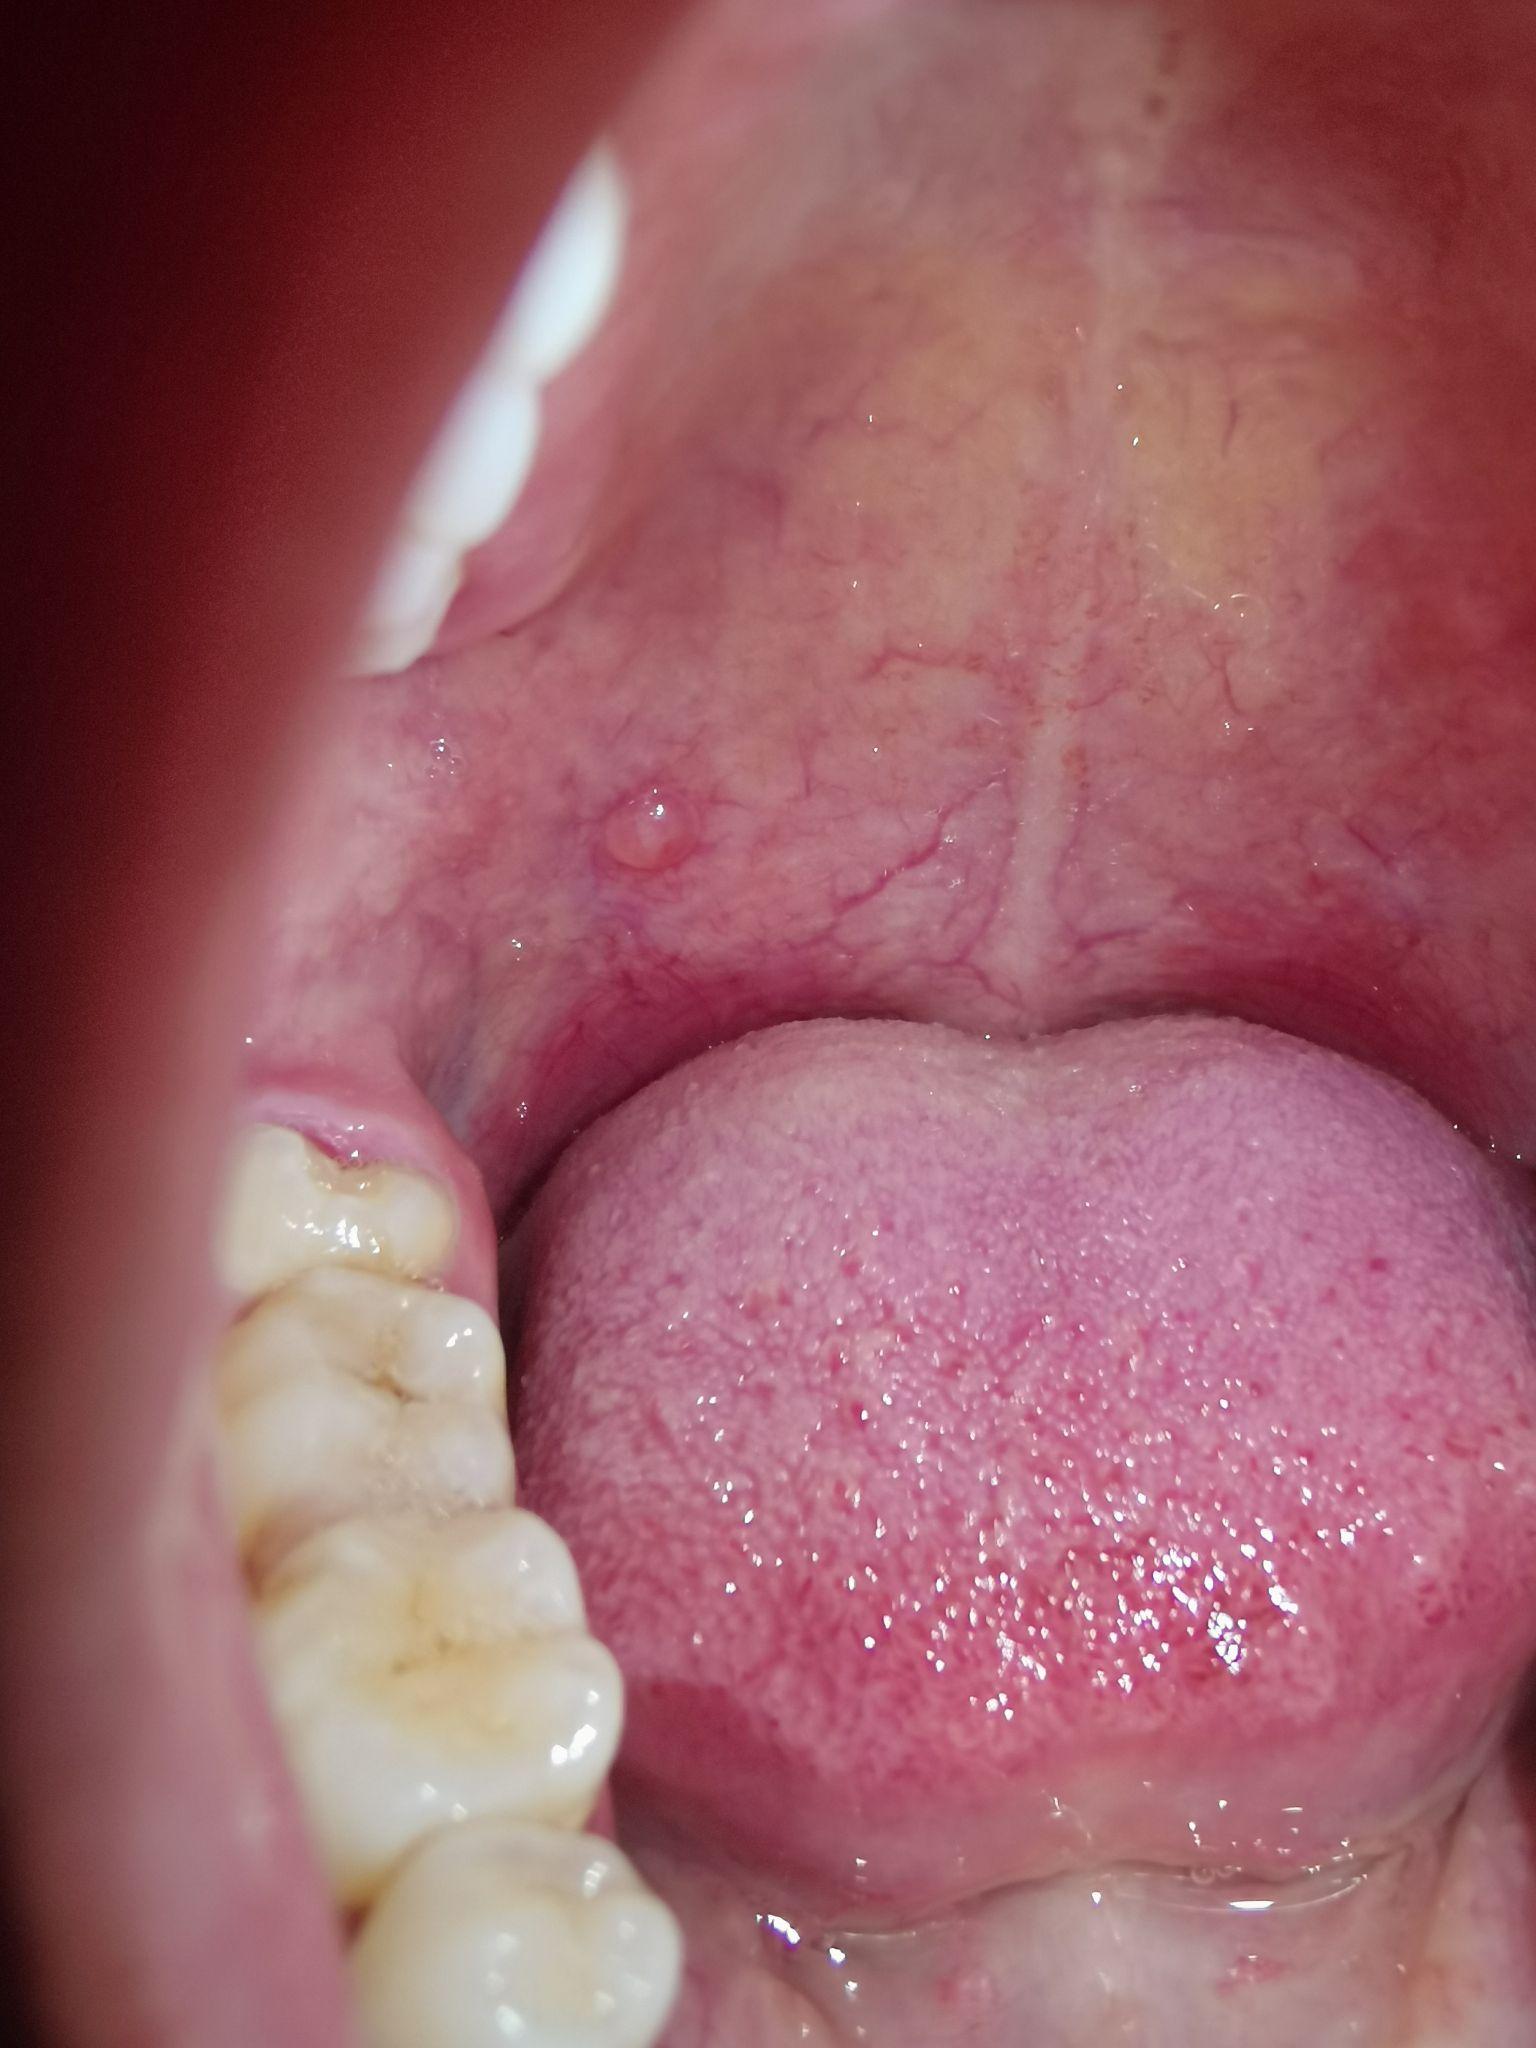

家里的亲戚上颚长了个肿物,不痛不痒,不红,想请问一下是什么东西

上颚长个红色的疙瘩,请指导下这个是什么疾病呢?(急) [病例帖]

上颚长了一个疙瘩,不会痛,也不影响吃饭那些,请问这是口腔癌前病变吗?

上颚长了一个类似瘤的东西不痛不痒,这是怎么回事,不会是癌把